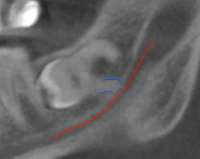

изображение.png (60Кб, 308x245)

308x245

Ну почему я такой неудачник? На снимке (у врача получалось лучше, я не смогу поймать ракурс) красным отмечен нижнечелюстной нерв, синим корень сраной восьмёрки. Из-за этого в обычной стоматологичке отказались удалять, и вообще есть шанс парализации части хари.